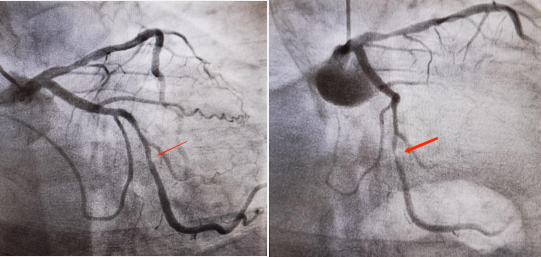

2021年5月17日,因胸痛入院,诊断急性冠脉综合征。冠脉造影显示原回旋支病变较前加重。

2022年3月20日,因反复胸闷、心悸2+年,加重1月入院。诊断为持续性心房颤动、冠状动脉粥样硬化性心脏病、劳力性心绞痛、心力衰竭、单支病变累及回旋支、回旋支支架植入术后、心功能Ⅲ级(NYHA分级)、腔隙性脑梗死、痛风。